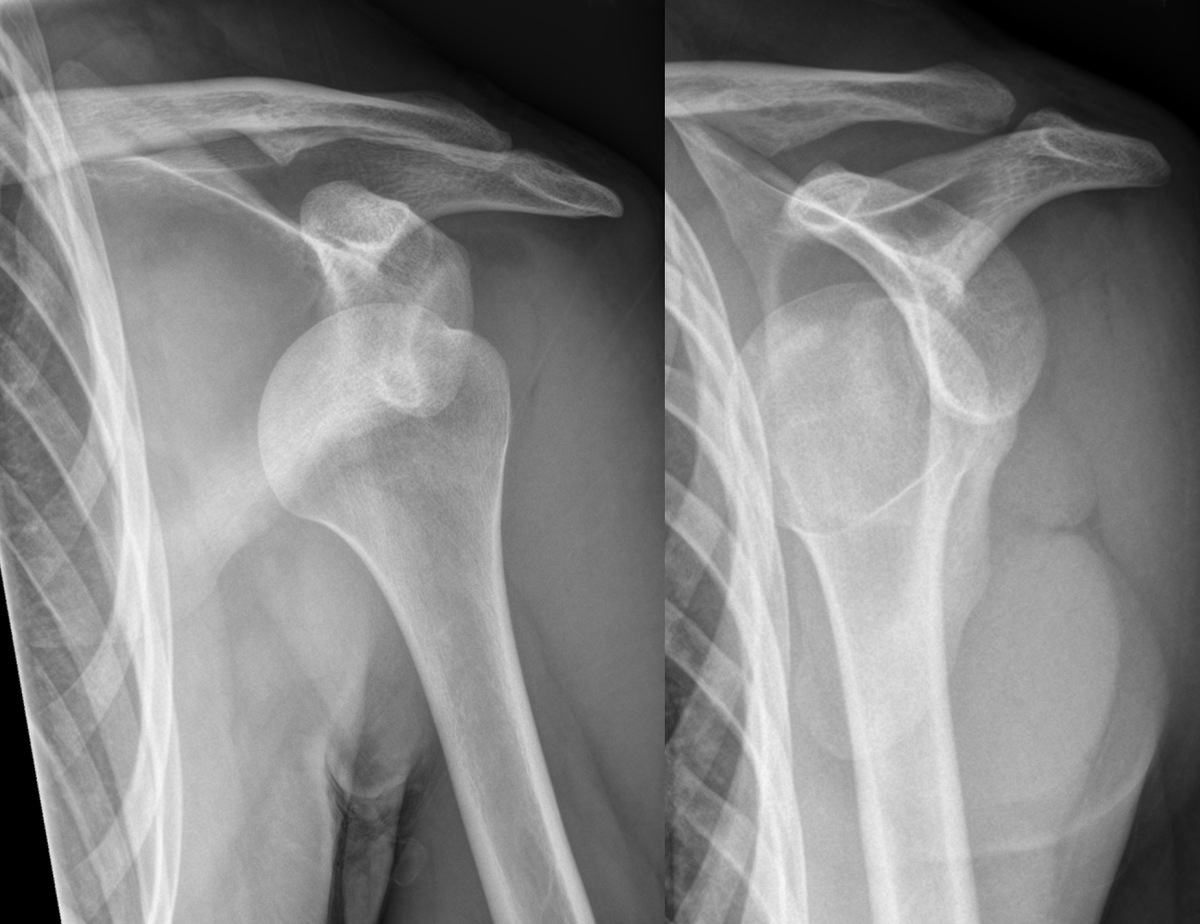

What will a AP view plain XR show in an ANTERIOR shoulder dislocation?

What will a AP view plain XR show in a POSTERIOR shoulder dislocation? (2 things)

What is a Lat view plain XR used for in a shoulder dislocation?

To differentiate between ANT + POST dislocations